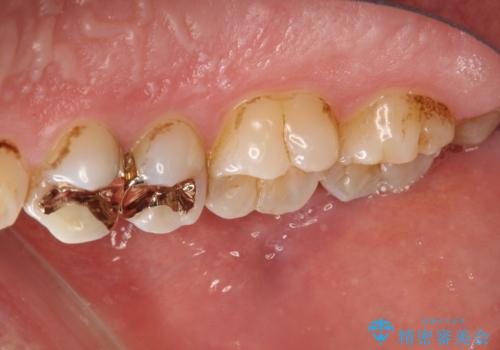

- 約3年ほど歯科医院での定期健診やクリーニングを受けてないとのことでした。全体的に歯石・着色などが付着していていたためPMTC60分コースを行いました。

分厚く歯石や着色が付着していると、汚れなのか虫歯なのかの判別がしづらい場合があります。しばらく定期健診やクリーニングを行っていない場合は、まずはしっかりと汚れを除去し、本来のご自身の歯の状態にすることで、より精密なお口の状態の診断が行えます。

CRは経年的に劣化や変色、着色が付着してしまうことがあります。

PMTCによって、CRと、ご自身の歯の境目の着色などがしっかりと落とせて目立たなくなる場合と、PMTCによってしっかりとクリーニングを行うと、CR自体が古く劣化・変色などしていて目立ってくる場合があります。気になる際は詰め替えを行います。